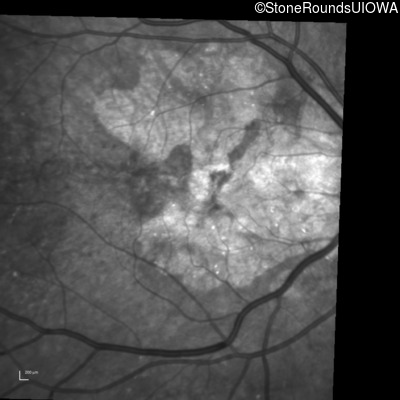

Infrared Fundus Photograph - Left - 20/20 -2

Exemplar